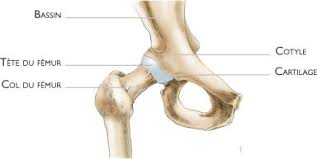

La prothèse de hanche est une des interventions majeures en orthopédie. Gr?ce au traitement antalgique, l'op?r? L'indication d'une reprise totale de hanche est portée la plupart du temps, dans le cas d'une faillite mécanique des implants.

La reprise du volant est envisageable après le 2ème mois en cas de reconstruction du cotyle et après le 3ème mois pour le fémur.

La nécessité d'une prothèse de hanche intervient pour diverse raison. Fracture du fémur prothésé (chute). Complications tardives des proth2ses de hanche.